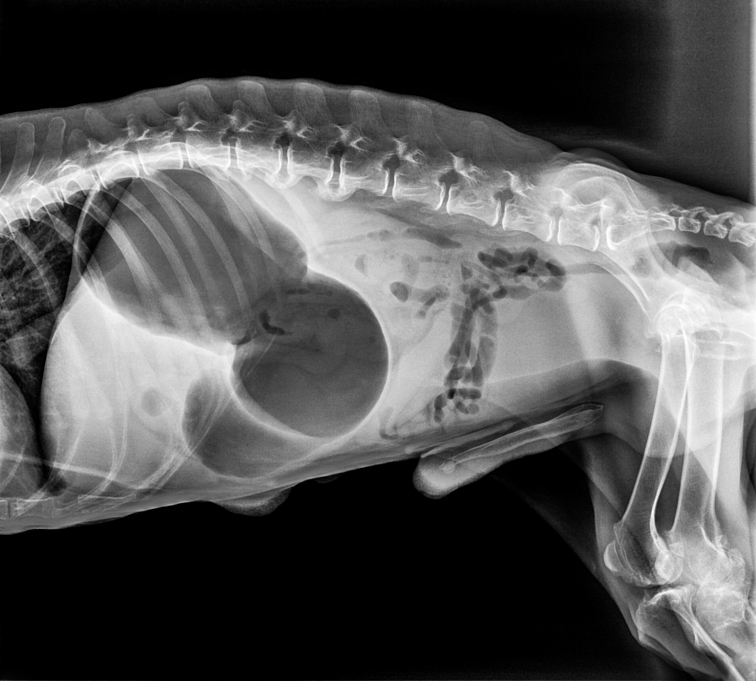

pes sa rýchlo naje granulami, ktoré bobtnajú, napije sa, alebo prehltné veľa vzduchu (aerofágia) a žalúdok sa začne rozťahovať, tzv. dilatácia.Otočenie žalúdka (volvulus)

žalúdok sa roztiahne a otočí o 180–360 stupňov. Tým sa uzavrú vstup (otvor z pažeráka) a výstup (otvor do dvanástnika, lat. duodenum). Plyn spolu s obsahom žalúdka sa nemôže dostať von a hromadí sa tam.Tlak na cievy a orgány